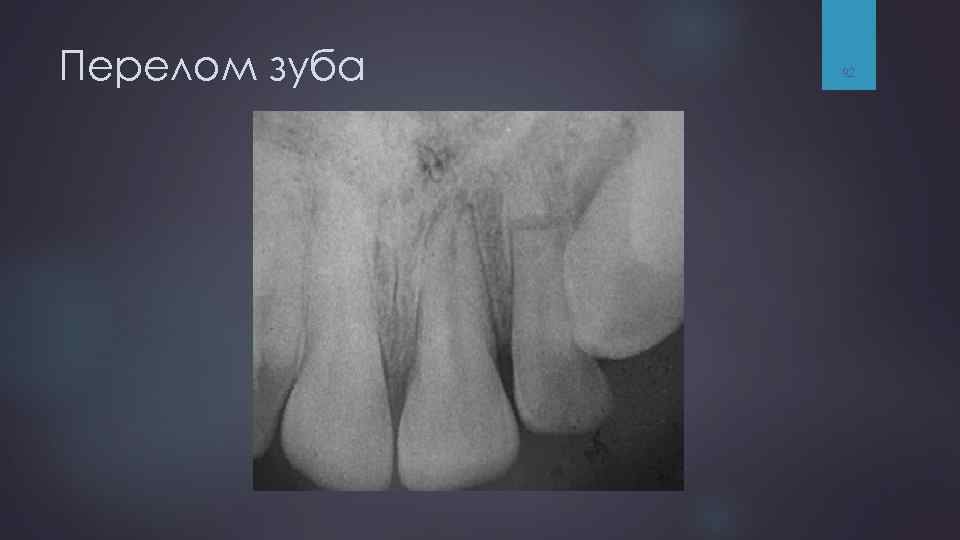

Перелом зуба — нарушение его целостности вследствие механического воздействия. Травма зубов может сопровождаться разрушением лунки зуба, переломами альвеолярного отростка или челюстей. Перелом зуба чаще встречается на верхней челюсти (центральный и боковой резцы), реже - нижней. Перелом других зубов встречается редко. Переломы нескольких зубов (в том числе премоляров и моляров) могут быть вследствие производственной или автомобильной травмы. 88

Перелом зуба 92

Классификация переломов зубов 1) переломы неполные (без вскрытия пульпы): а) трещины эмали и дентина; б) краевой перелом коронки в зоне эмали; в) краевой перелом коронки в зоне эмали и дентин; 2) переломы полные (со вскрытием пульпы) открытые и закрытые: а) шейки зуба; б) корня; в) верхушки корня. 93

Перелом зуба и осложнение 94

Рентгенограмма переднего отдела нижней челюсти вприкус. Открытый перелом альвеолярной части в области 2. 1 -1. 2 со смещением отломка.

Внутриротовая рентгенограмма переднего отдела верхней челюсти вприкус. Поперечный перелом корня 21 зубы шинированы.